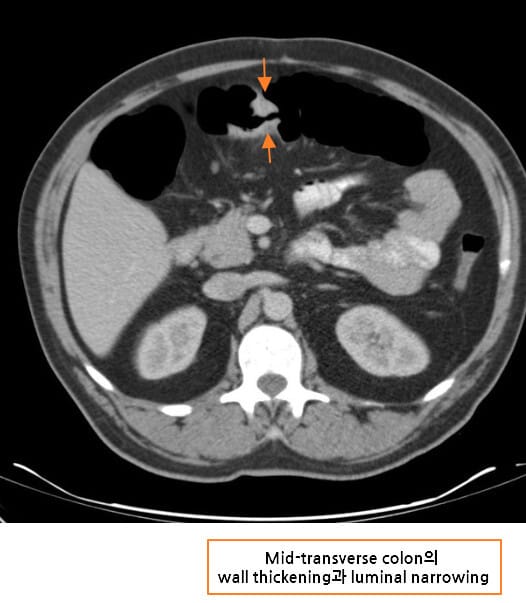

CT 소견 (Contrast-enhanced CT)

🔵 장벽 비후 (Bowel wall thickening)

암 부위의 장벽이 국소적으로 두꺼워지며, 조영증강되는 불균일한 덩어리로 관찰됩니다.

🔵 Annular constricting mass

암이 장을 원형으로 둘러싸며 협착을 유발하는 고전적 폐색 패턴입니다.

Niknejad M, Colon cancer. Case study, Radiopaedia.org (Accessed on 15 Jul 2025) https://doi.org/10.53347/rID-87193